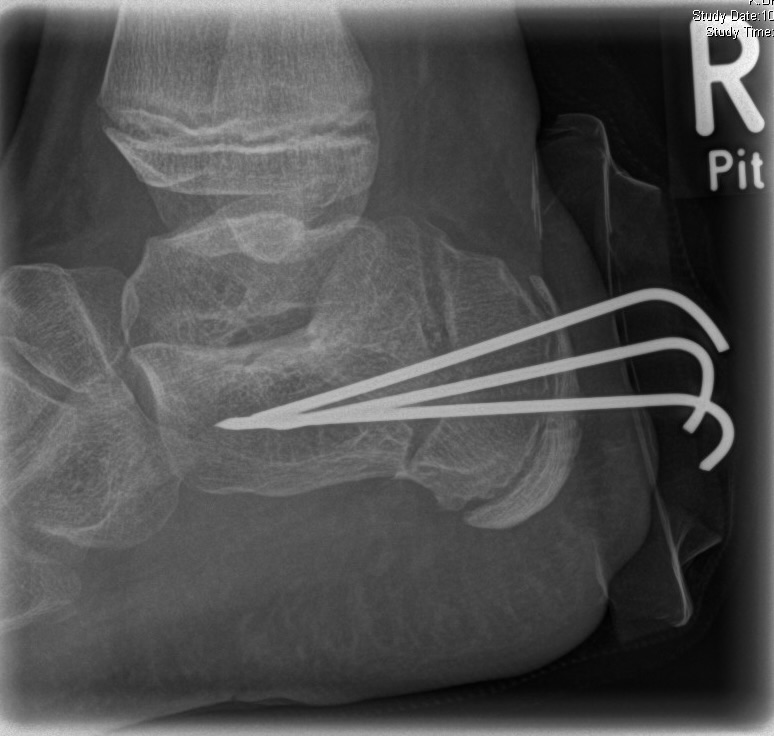

Zusätzlich schränken Wachstumsfugen die Wahl der Osteosynthese ein. Eine die Fuge kreuzende Osteosynthese ist ausschließlich mit Kirschner-Drähten möglich (Abb. 3).

Abb. 3 a-j: Beispiel einer Calcaneusverschiebeosteotomie mit offenen Wachstumsfugen und der entsprechenden Osteosynthese mit Kirschner Drähten. Lokalisation der Osteotomie (a), Lage der Fräse (b-d), Drahtlage mehrere Ansichten (e-h), Heilung der Osteotomie 4 Wochen postoperativ und Entfernung der Drähte (i-j).

Zum Lesen der Bildbeschreibung und zur Vollansicht bitte die Bilder anklicken. Bilder: A. Helmers.